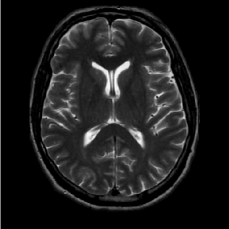

(a) Shepp-Logan phantom

Refer to caption

(b) FLAIT brain

(c) Lumbar spine

(d) Circle of Willis

Figure 2: Test Images.

We turn now to test TDIHT for high dimensional signals. We test the performance of several MRI images: the Shepp-Logan phantom, FLAIT brain image, T2 Sagittal view of the lumbar spine and the circle of Willis. The first image is of size 256×256256256256\times 256, while the other are of size 512×512512512512\times 512. They are all presented in Fig. 2.

We focus on the recovery of these images from a few number of Fourier measurements. With 𝛀𝛀{\mathbf{\Omega}} set to be the undecimated Haar transform with one level of resolution (redundancy four) and 𝐃𝐃\mathbf{D} its inverse transform, we succeed to recover the phantom image using only 181818 sampled radial lines, which is only 6.5%percent6.56.5\% of the measurements. This number is only slightly larger than the number needed for GAP, relaxed ASP (RASP) and Relaxed ACoSaMP (RACoSaMP) in [10, 38]. The advantage of TDIHT over these methods is its low complexity as it requires applying only 𝐌𝐌{\mathbf{M}} and its conjugate and 𝛀𝛀{\mathbf{\Omega}} and its inverse transform while in the other algorithms a high dimensional least squares minimization problem should be solved. Note also that for AIHT and RAHTP the number of radial lines needed for recovery is 353535 and for IHT (with the decimated Haar operator with one level of resolution) we need more than 505050 radial lines.